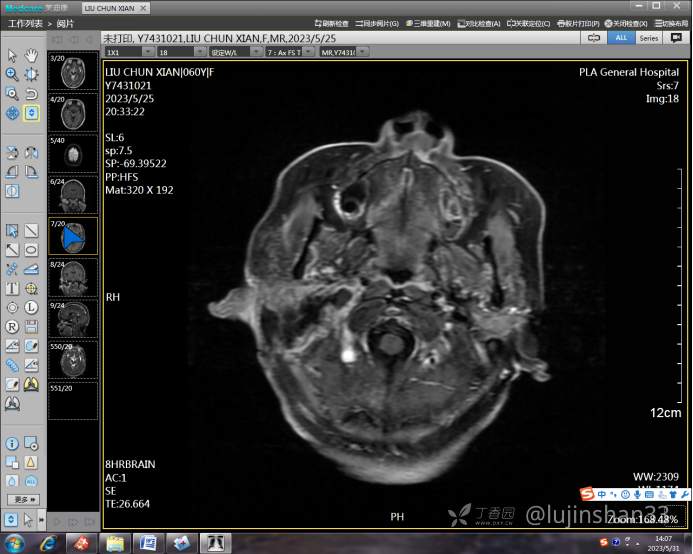

(2023-05-15 10:00,本院)行磁共振(颅脑)检查提示:右侧乳突区异常信号,考虑恶性、软骨来源肿瘤,软骨肉瘤可能性大。(集体讨论意见);脑内散在多发缺血灶。

术后复查MRI: